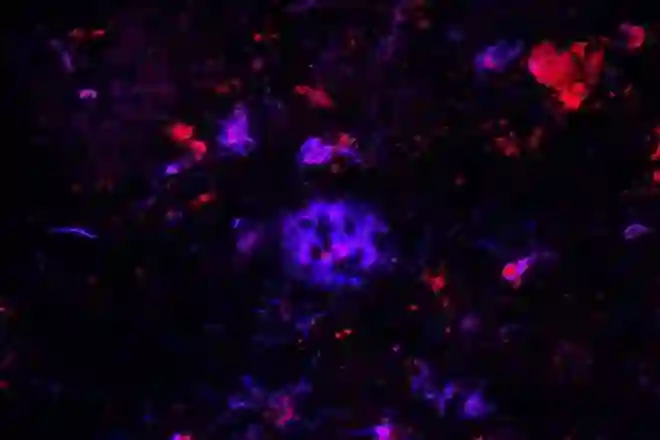

Antibodies against APOE (red) bind to amyloid plaques (blue) in brain tissue from people with Alzheimer's disease. Researchers have found that the antibody can sweep away the damaging plaques, at least in mice, which could lead to a therapy for the devastating disease. Credit: Monica Xiong